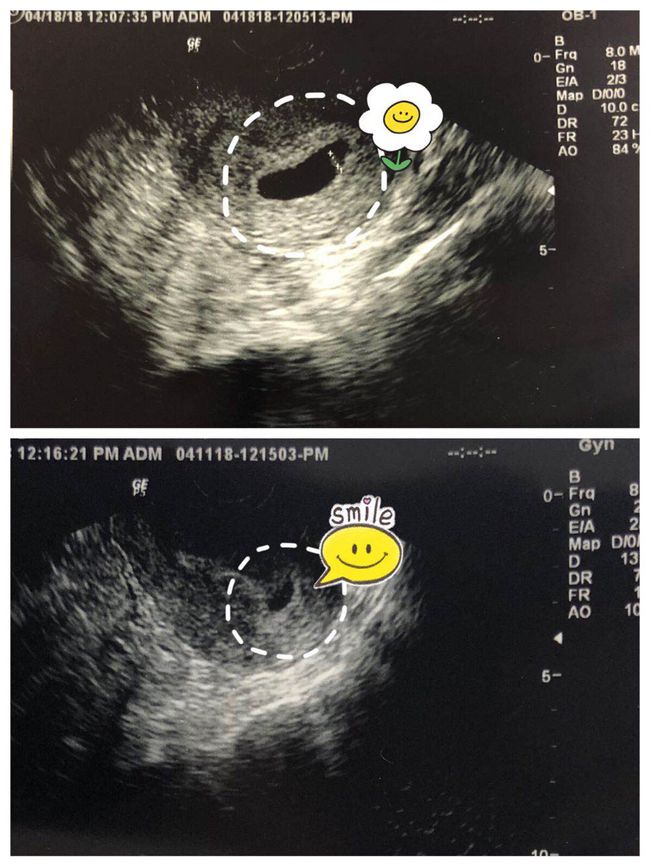

胎位横位是指胎儿在母体内呈横向位置,这种情况下,胎儿头部和臀部分别位于子宫两侧,容易导致难产。胎位横位不仅给分娩带来困难,还可能增加母婴并发症的风险,如胎儿窘迫、新生儿窒息等。